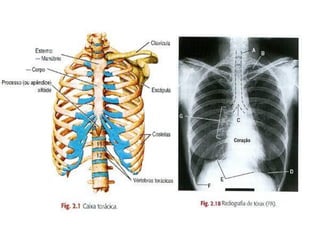

TÓRAX

ESTERNO

COSTELAS

COSTELA